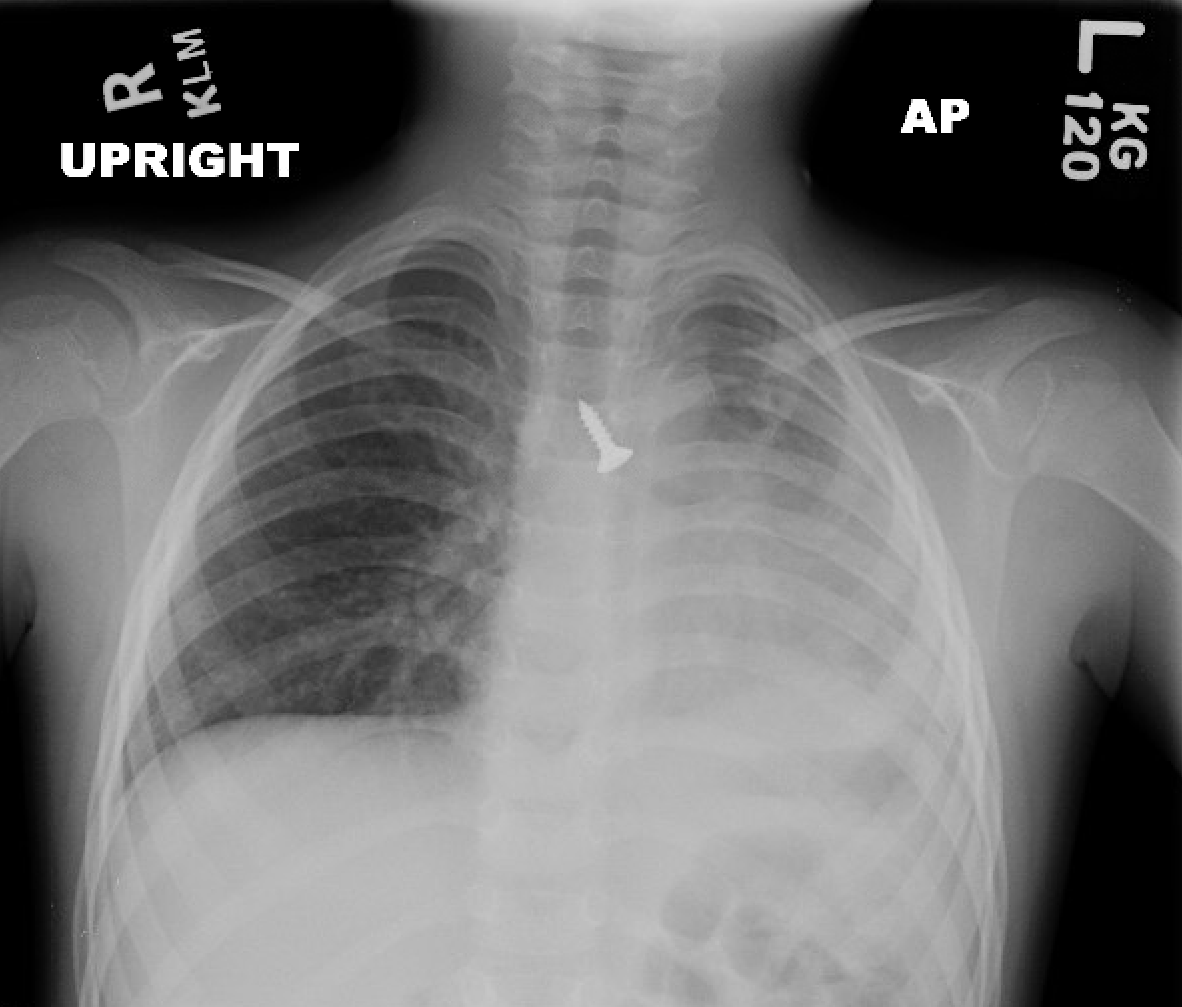

The following chest x-ray was obtained:

Figure 1: Upright AP Chest radiograph demonstrating a foreign body at the level of the carina

On examination in the Emergency Department, she is well appearing, tachypnic, but in no respiratory distress, and has no voice change or audible respiratory sounds. There are normal breath sounds throughout the right chest. Breath sounds are absent on the left. The trachea is midline, and there is no crepitus.

The history and examination is highly suspicious for an aspirated foreign body, but there is also concern for pneumothorax and hemothorax, especially given the report of an improperly applied Heimlich maneuver to the chest.